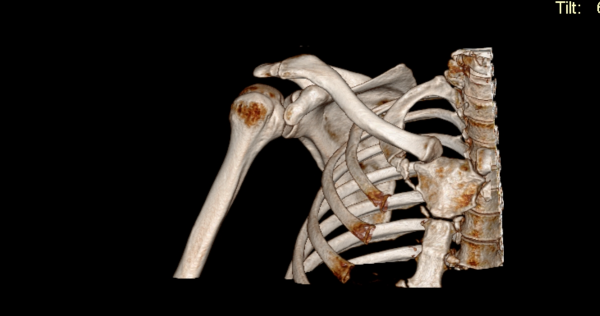

КТ — это мега-продвинутый рентген. Там используется тот же принцип: трубка посылает x-ray излучение, оно проходит сквозь тело и его ловит датчик. Вся эта система может вращаться и по ходу работы делает огромное число снимков. Эти снимки “сшиваются” в единую 3D-модель, которую потом можно детально покрутить на компьютере.

КТ плечевого сустава

В чем сила КТ? Разные ткани по-разному поглощают излучение: кость — сильно, мышцы — меньше, воздух — почти совсем нет. На выходе мы получаем детальную модель человеческого тела с большим акцентом на скелет.

Хотя компьютерный томограф видит отдельные органы и мягкие ткани, он все же уступает в этом аппарату МРТ. Зато когда есть подозрение, что откололся крошечный кусок кости и надо проверить куда он делся и точно ли откололся — это про КТ.

Я прошел и КТ, после чего посмотрел (с монитора врача) на свой грудной отдел в 3D. Мне показали тот самый кусочек кости, что откололся и больше не поддерживает мой сустав в стабильном состоянии. Вердикт был однозначный — операция. Правда обещают, что спустя шесть месяцев буду лучше, чем был до.